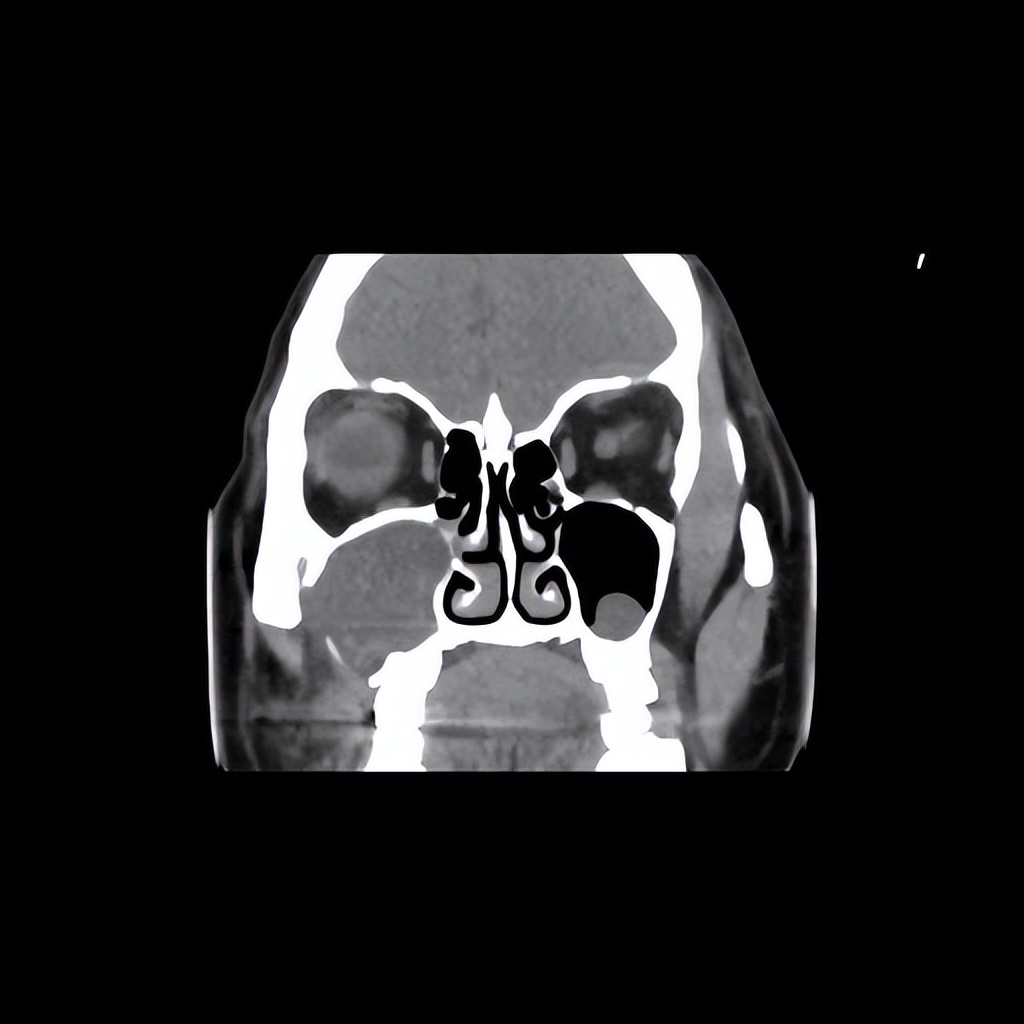

来佛山复星禅诚医院耳鼻喉行鼻窦CT提示“右侧上颌窦内新生物,性质待查”门诊拟“上颌窦炎”收住我科。

由于CT显示患者的骨质有破坏,病情相对严重,给予安排鼻内镜上颌窦微创手术治疗。插管全麻后就开始了手术,在鼻内镜下开放右侧上颌窦口后,可见上颌窦内巨大的骨囊肿,考虑是上颌骨牙槽突的骨囊肿,突入右侧上颌窦,术中予以彻底清除囊肿。